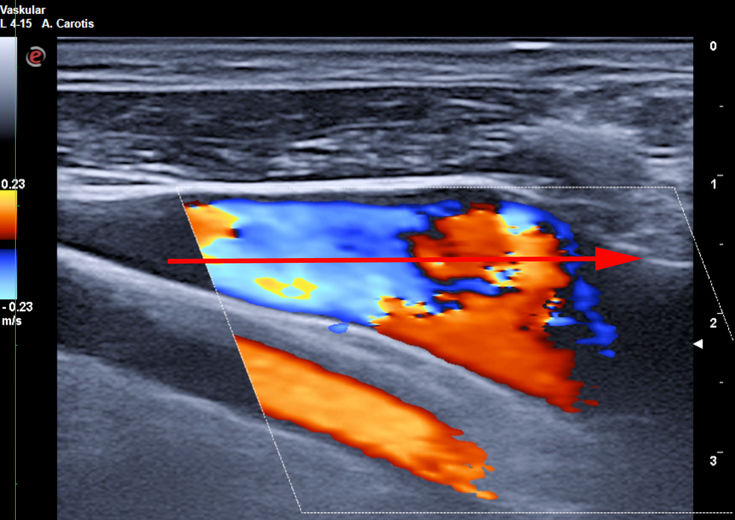

Die in der Anästhesie verbreitete Punktion der distalen Vena jugularis ist komplikationsträchtig und sollte vermieden werden. Normalerweise liegt die Vena jugularis lateral der A. carotis.

Bei der schädelnahen Punktion muß der Kopf nach links gedreht werden, weil sonst das Kinn im Weg ist. Dadurch rotiert die Vene vor die Arterie und das Lumen wird schlitzförmig.

Vor der Einmündung in die Vena anonyma macht die Jugularvene einen Knick von 45 Grad nach dorsal. Diatator, Einführschleuse und Katheter stoßen dort an der Venenvorderwand an und erzeugen Intimaläsionen, die bei 30% der Patienten später zur Thrombose führen.

Darüberhinaus geht der Katheter durch die ganze Breite des Musculus sternocleidomastoideus. Dies führt zu einer rein/raus-Bewegung des Katheters bei jedem Schlucken und jeder Kopfbewegung. Das begünstigt einerseits das Einwandern von Hautkeimen in den Punktionskanal, andererseits werden Fibrinablagerungen auf der Katheteroberfläche an der Punktionsstelle abgestreift. Dadurch kommt es zu einer Akkumulation von Fibrin und thrombotischem Material an der Venenwand und um den Katheter.